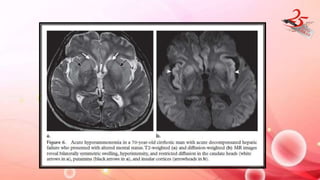

LIVER DISEASE

• CAUSATIVE AGENT : Due to nitrogenous waste crossing BBB

• CLINICAL FEATURES : cirrhosis with portal htn /iatrogenic (TIPSS)

• IMAGING FINDINGS :

- GP and SN : hyper on T1( due to Mn deposn)

- Reversible post transplantation.

- Acute hyperammonemia : bilaterally symmetric swelling, T2

prolongation restricted diffusion in the basal ganglia, insular cortex,

and cingulate gyrus

- MRS : Detection of glutamate-glutamine